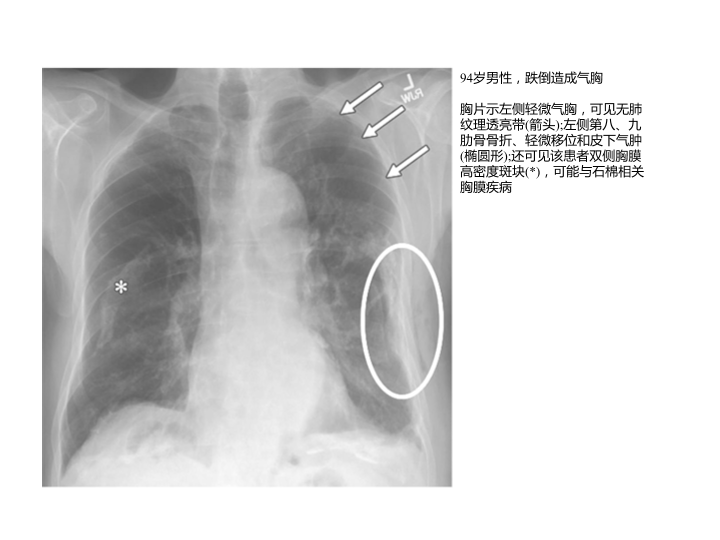

胸部外伤及胸腔积液处理